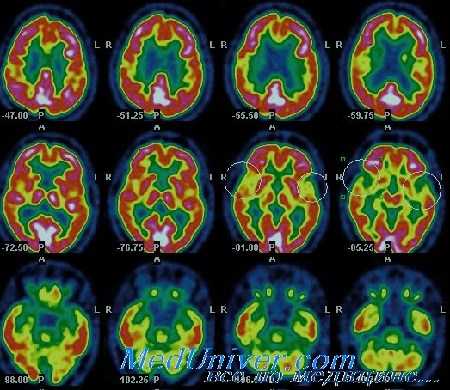

ПЭТ в мониторинге регионарного мозгового кровотока

• Более затратный и комплексный метод, чем однофотонная эмиссионная компьютерная томография, но с более широкими возможностями применения.

• Измеряется региональный кровоток, объем крови, потребление кислорода мозгом, фракция экстракции кислорода, метаболизм глюкозы (зависит от используемого изотопа).

• Томограммыснимаются после введения 'флюоро-дезоксиглюкозы или изотопа кислорода-15. Эти изотопы затем могут комбинироваться с маркерами специфического нейронального повреждения.

Преимущества ПЭТ:

• Возможность повторения исследования для подтверждения эффекта лечения.

• Возможность подсчитать фракцию экстракции кислорода и получить информацию о объеме ишемического очага.

Недостатки ПЭТ:

• В сфере исследований возможности применения ограничены из-за необходимости в циклотроне.

• Дорогой, не везде доступен.

• Требует транспортировки пациента к сканеру.

• Отсутствует возможность непрерывного исследования

Особенности применения ПЭТ:

• Может быть использована в ранние сроки для прогнозирования исхода — снижение церебральной перфузии коррелирует с неблагоприятным исходом (даже в случае, если ВЧД пока остается в норме)

• Исследования продемонстрировали увеличение объема мозга в области ишемии па фоне гипервентиляции, несмотря на «улучшение» глобальных параметров.